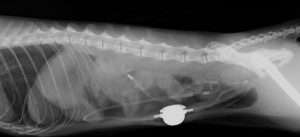

膀胱結石

緑の円内にあるのが結石です。